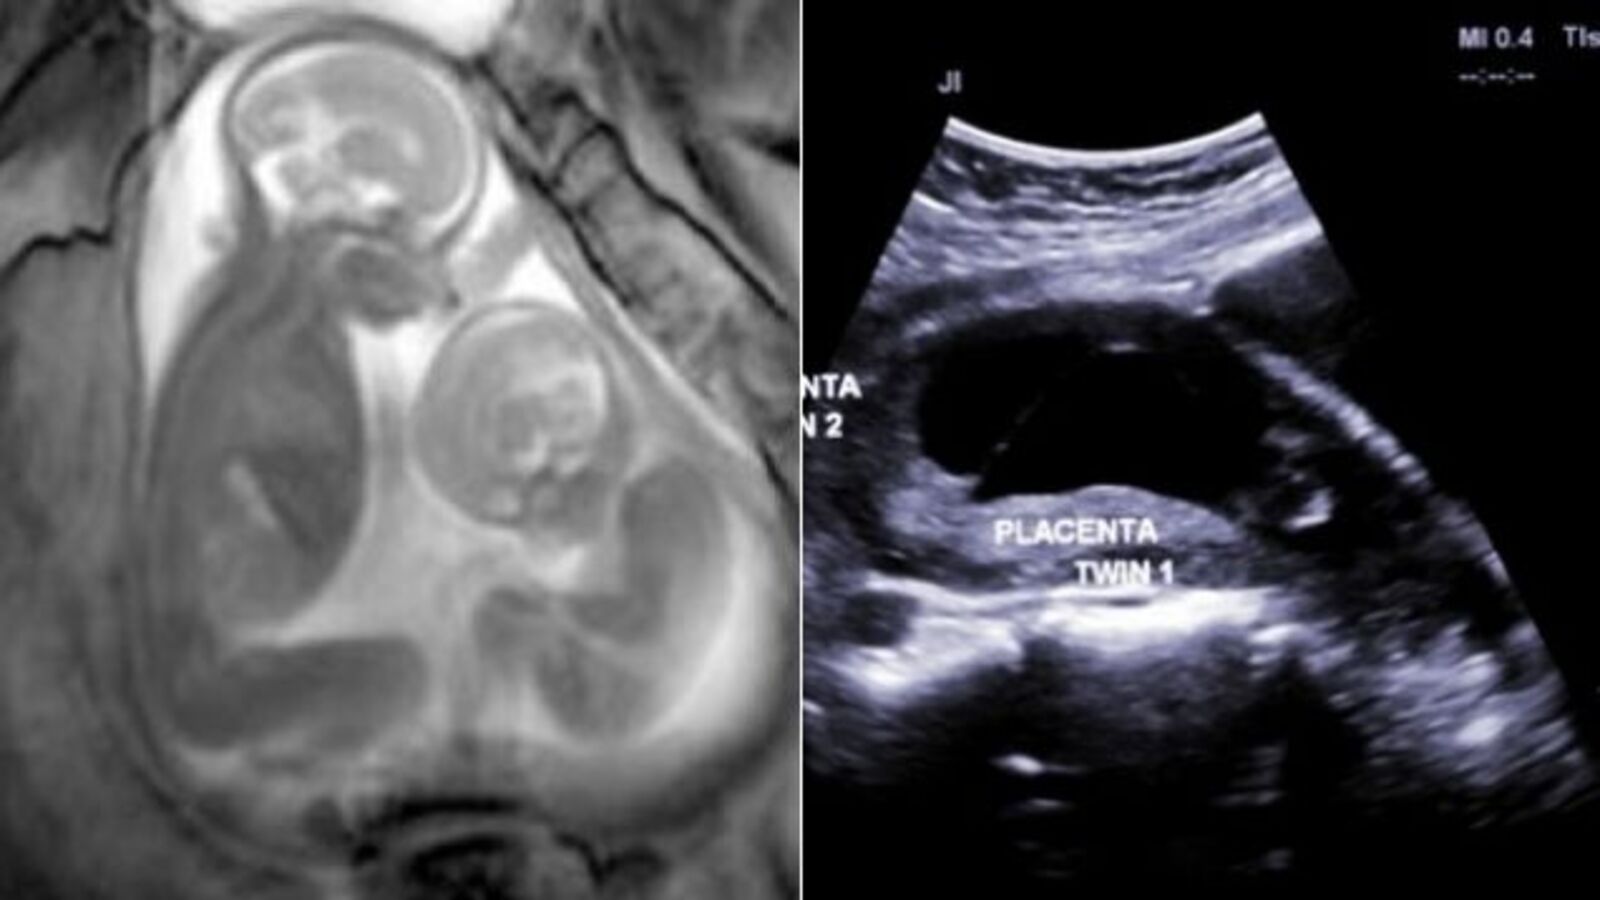

Baby Mri Scan Video. What they done was put a small needle in his foot to give him the drugs to make him sleep, and anymore if needed, then lay still for about 1/2 hour and go through a machine like a dognut, it is very noisy, but i am sure the parents stress more than the kids. With thanks to mary for letting us use this clip. Watch this incredible video of an mri scan of an unborn baby in the womb. In the video footage from the scan, you see the baby moving around all over the place;

She has very little room and can�t straighten her legs. Mri scan video of baby in the womb. An mri scan shows an unborn baby at 37 weeks. As the medical education director for an mri clinic in vancouver, bc, canada i wanted to offer my assurance regarding your question relating to the safety of having an mri done while pregnant. Generally, babies tend to fall. She seems to be trying to get comfortable.

He shared a number of mri scans with his fans, revealing what babies look like as they grow. This caused the mother�s belly to wobble. This is a video of my son sneezing inside the womb whilst he was being scanned by an mri machine. Unlike ultrasounds, the high tech scan shows beneath the baby’s skin and beats normal mri scanners by using complex technology to get usable images from even the wriggliest babies. In the video below you can even see each of the tiny chambers and valves of the baby’s heart (smaller than a penny at this age.

A doctor has revealed the reason why pregnant women are unlikely to be shown an mri scan of their baby. She seems to be trying to get comfortable. However, very few researchers have taken on the challenge of trying to scan babies’ brains, especially while they are awake. Mris of babies that look like demons go viral. Watch how the foetus jumps around the inside the womb in mri scan footage researchers have produced unprecedented images of a baby�s heart while it is still inside the womb.

The image behind me is an mri of a baby during pregnancy, and, yeah., the doc said in a video that has now gone viral. My little boy had to have an mri scan done at 5 months old. “babies and mri machines have very different needs,” saxe points out. Scientists supported by the oxford biomedical research centre used a xenon gas scan to pick up. A doctor has revealed the reason why pregnant women are unlikely to be shown an mri scan of their baby.

He shared a number of mri scans with his fans, revealing what babies look like as they grow. The image behind me is an mri of a baby during pregnancy, and, yeah., the doc said in a video that has now gone viral. What they done was put a small needle in his foot to give him the drugs to make him sleep, and anymore if needed, then lay still for about 1/2 hour and go through a machine like a dognut, it is very noisy, but i am sure the parents stress more than the kids. In a video to his channel, he explains that babies tend to look really, really weird when they are in the womb. The baby can be seen jumping around, stretching, and even giving his mother a good kick.

So although a scan would be entirely safe, mri is quite literally out of bounds. Scientists supported by the oxford biomedical research centre used a xenon gas scan to pick up. As the medical education director for an mri clinic in vancouver, bc, canada i wanted to offer my assurance regarding your question relating to the safety of having an mri done while pregnant. The video has been popular across social media networks and has been given to channelmum.com to share with mothers around the world. Unlike ultrasounds, the high tech scan shows beneath the baby’s skin and beats normal mri scanners by using complex technology to get usable images from even the wriggliest babies.